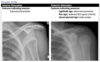

Anterior vs posterior shoulder dislocation on XR

99

Anterior shoulder dislocation

100

Posterior shoulder dislocation

101

Hill Sachs

102

Bankart lesion